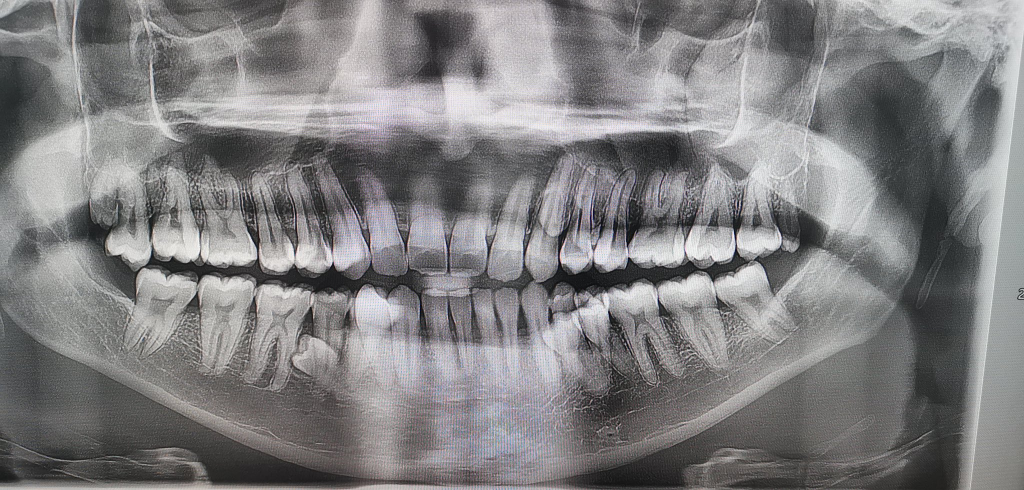

Prathab first noticed something unusual in 2021 during a casual family tea-time conversation. After counting together, they found he had 38 teeth at the time. A dental X-ray later revealed four additional unerupted teeth, bringing the total to 42 by early 2023. Fortunately, most of his teeth grew normally without complications.

His record was officially confirmed in 2023 after examinations by two dentists. What makes his case even more remarkable is that, beyond the visible teeth, two more remain unerupted.

He has 2 more teeth yet to erupt